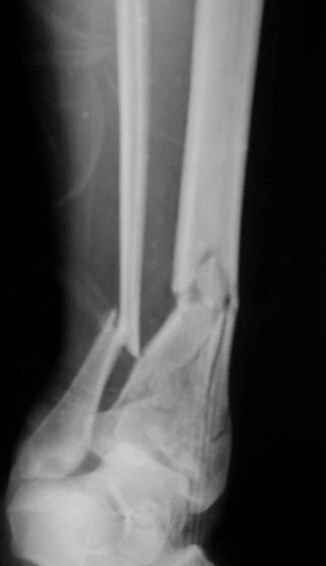

Открытый оскольчатый перелом н/3 голени.

Здравствуйте, коллеги! 16/10/06 г. В отделение поступила больная с производственной травмой - Открытый оскольчатый перелом метафиза и метадиафиза обеих костей правой голени со смещением отлоков.

При поступлении произведено ПХО ран, наложена система скелетного вытяжения за пяточную кость. Проводилась антибактериальная терапия, перевязки. На данный момент раны зажили первичным натяжением, швы сняты. Сохраняется лёгкая гиперемия в области одной из ран. Планируя оперативное лечение хотелось бы узнать Ваше мнение о наиболее рациональном методе лечения данного перелома.

Здравствуйте коллеги! В данной ситуации я полностью согласен с мнением Александра Николаевича! Практически любой внутрисуставной(тем более приведенный на снимках) перелом требует открытой репозиции.Судя по приведенным рентгенограммам, в области дистального тибио-фибулярного сочленения имеется "минус" ткань на tibia, которая может потребовать костной пластики.Метод фиксации любой,главное ранние движения в суставе. С уважением Руслан Ш.

К слову, тема этого обсуждения обозначена неточно, тут перелом дистального суставного конца типа 43-C, а не "открытый оскольчатый перелом н/3 голени", т.е. диафизарный, 42-.

Действительно, речь идет о сложном внутрисуставном, да еще и открытом переломе 43С.3.

1. Представленные рентгенограммы во-превых плохого качества (ну да ерунда), а во-вторых (самое главное) - в нестандартных проекциях. Невозможно оценить количество и положение фрагментов суставной поврехности. Собственно это делает обсуждение бессмысленным. Мы обсуждаем не конкретный случай, а вообще...